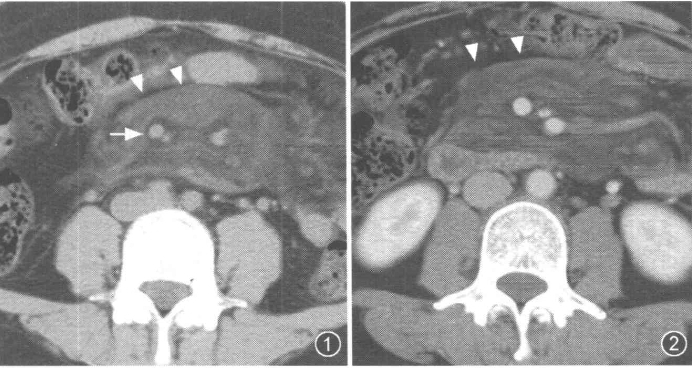

2、靶征(肠壁)

主要见于腹部增强扫描,增后的肠壁表现为三层结构,内层和外层是高密度强化层,两者之间是低密度的中间层。

靶征出现于可导致长鼻粘膜水肿、炎症或两者同时存在的多种肠管病变。其内层代表粘膜层,外层代表固有层和浆膜层,由于对比剂的强化而成高密度,中层的低密度被认为是由于粘膜下层水肿所致。靶征的出现提示粘膜和固有层、浆膜层的充血并伴有粘膜下水肿和炎症。颈静脉注射对比剂后,各层之间的密度差异在动脉早期和门晚期表现最为清楚,如果对比剂注入速度太慢、剂量太少以及延时超过2分钟,此征根本不出现。但是当粘膜下水肿非常严重时,CT平扫也可能出现。如果肠管内充满水而使肠管扩张时,靶征显示更为清楚。

CT扫描时,良性的肠管病变通常表现为肠壁的环形均匀性增厚,厚度从粘膜面到浆膜面一般不超过1公分,根据病因和病变严重程度的不同,偶尔可能超过1公分,但一般在2公分以内。肠壁出现靶征的病变主要见于缺血性肠病、小肠壁内出血、克隆氏病、溃疡性结肠炎、血管性疾病、感染性疾病、放射疾病和门脉高压所致肠粘膜水肿等。靶征并不是一个特异征象,但是在恶性病变中一般不出现此征,只是浸润性直肠癌是一个例外。

所以,一般情况下,靶征的出现,首先要考虑的是肠道的炎症性病变。

以下是空谷幽兰斑竹曾经发过的一个帖子,靶征非常典型:

系统性红斑狼疮